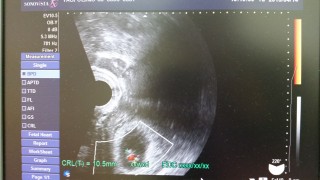

BTで授かっています。前週に胎芽、卵黄嚢、心拍確認。どれだけ大きくなってるかという今回はCRL8.52mmと小さい感じでしたが、特に何も言われないし、心拍もあるし、位置や向きのせいだろうと思うことに。そして翌週には19mmと問題なし。出血もわずかに時々みられていましたが、問題なし。普通に長時間勤務、夜勤もしていました。つわりで辛いので休みの日は何もしていませんでしたが。

自分で数えて8w目頃。検査薬もわざと生理予定日から20日くらい我慢して(笑)2回とも陽性!!!!!(2016/2/15)昨日!!!初診行ってきました!!!!1人目BABYです!1発で心拍を確認したくてちょっと遅めに行ったら実際は7w5dでちょっとズレてましたが、12mmの二頭身!!無事確認できました!胸の張りや食べつわりっぽいのはありましたが、全然軽くて他のつわりもなかったので、長めに待って診察に行きました!つわりがきつい人はオススメしませんが汗心臓がすごいスピードで動いてて、エコー写真もらっ時はやっぱり感動するんですね(笑)このサイトはよく見てたので、皆さんからコウノトリ頂けたので♪私も送ります!

7w5d、約10mmの赤ちゃんです。無事に心拍も確認できて一安心!こんなちいさな体でも、心臓が一丁前にぱくぱくしててとても感動しました!